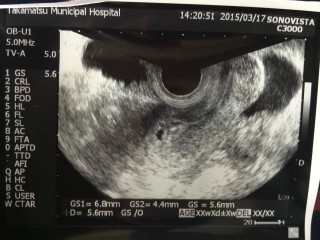

胎嚢2cm!右にズーム画像つけてくれました。

ちゃんと子宮に着床してるね~おめでとう。

でもここからが色々大変だからね!

と、釘を刺されました(^◇^;)

確かに~

また2w後に確認です。心音聴けるといいなぁ~(≧∇≦)